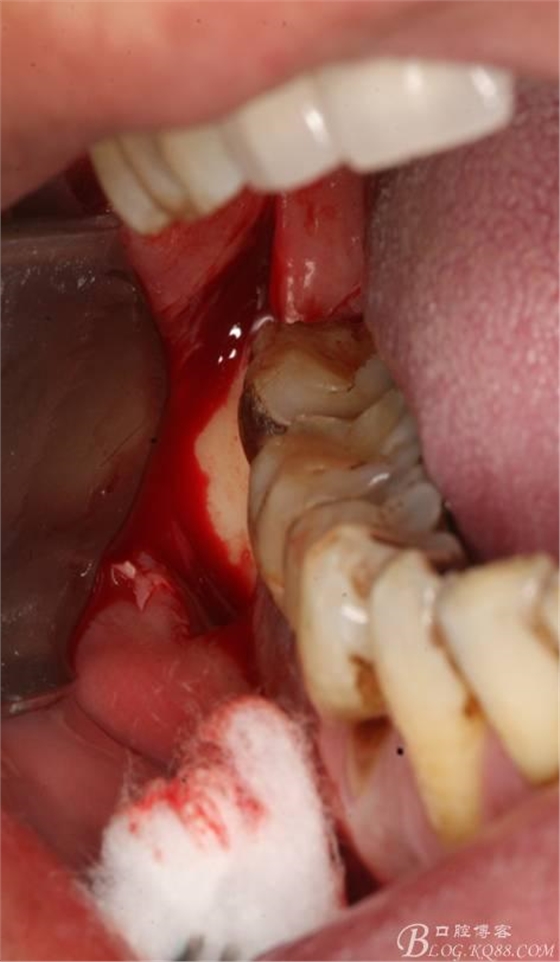

2.切開(kāi)翻瓣

3.去骨、暴露48.